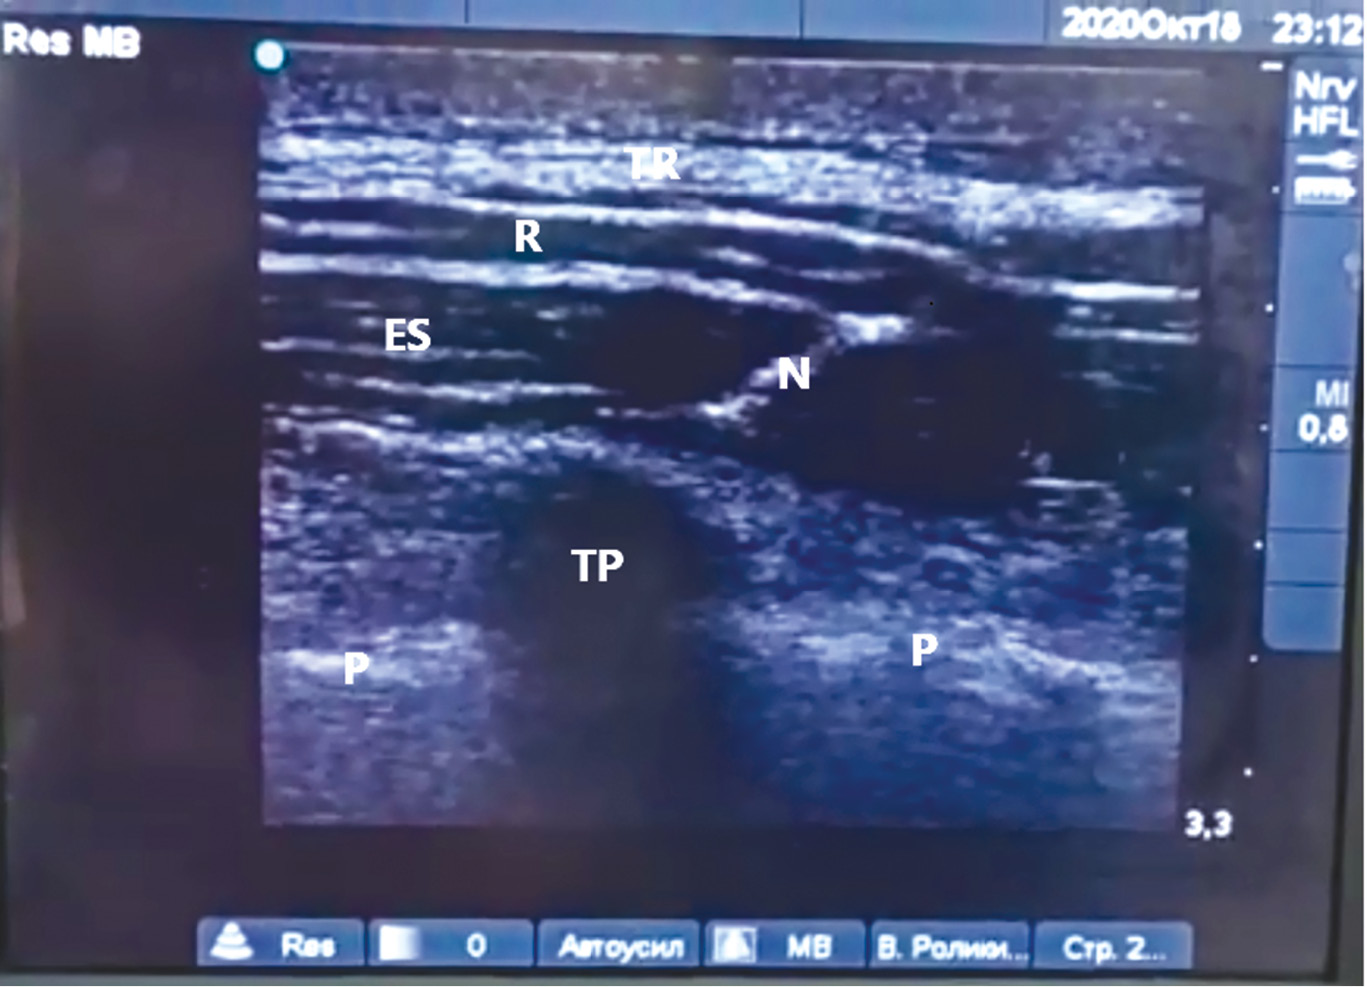

ESP-блок выполняли на уровне поперечного отростка Th5 позвонка. После размещения линейного датчика портативного ультразвукового аппарата параллельно позвоночному столбу примерно в 3 см латеральнее от него были визуализированы соседние поперечные отростки Th5 и Th6 позвонков, над которыми располагались трапециевидная мышца, большая ромбовидная мышца и мышца, выпрямляющая позвоночник. Игла 22G, к которой был присоединëн шприц с 20 мл 0,375% раствора левобупивакаина, была проведена в саггитальной плоскости краниокаудально под углом 45° в направлении поперечного отростка Th5 позвонка (рис. 1).

Рис. 1. УЗИ-картина костно-мышечно-связочного комплекса спины (T –трапециевидная мышца, RM – ромбовидная мышца, ESM – мышца, выпрямляющая позвоночник, TP – поперечный отросток, P – плевра, N – игла) / Fig. 1. Ultrasound picture of the musculoskeletal-ligamentous complex of the back (T – trapezius muscle, RM – rhomboid muscle, ESM – erector spine muscle, TP – transverse process, P – pleura, N – needle)

После прохождения кончиком иглы гиперэхогенной внутренней фасции m. erector spinae была выполнена предварительная быстрая инъекция 1 мл раствора местного анестетика. При эхоскопии наблюдалось отслоение внутренней фасции m. erector spinae от межпоперечной связки, что свидетельствовало о правильном положении кончика иглы, после чего были медленно введены оставшиеся 19 мл 0,375% раствора левобупивакаина. Через 30 мин с помощью теста «pin prick» оценивалось развитие сенсорного блока, который оказался достаточно обширным и распространялся c Th2 по Th9 дерматомы.